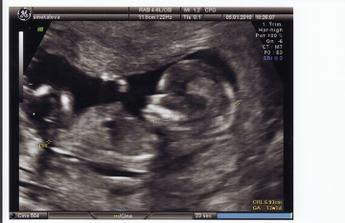

5.1.2010 - screeningové vyšetření nás stálo 1400 KČ, byla jsem objednaná na dobu mezi 15 - 20 h pro velký nával, čekali jsme od 15:30, na řadu jsem přišla v 18:30!!! Hladová, unavená a naštvaná na nejvyšší míru...

Miminko je ale v pořádku, podle PM jsme 13+5 tt, podle UZ 13+2 tt. TP stanovený na 11.7.2010. Další kontrolní UZ 23.2.2010